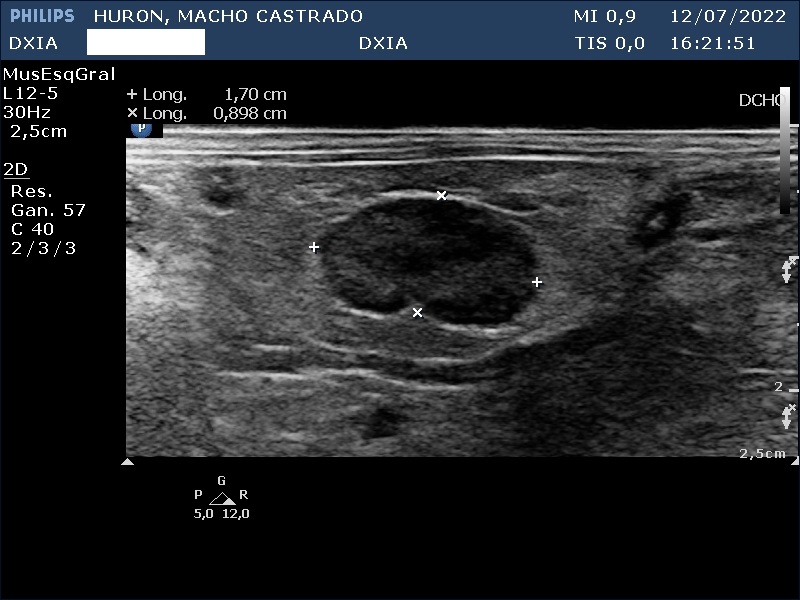

Hallazgos ecográficos